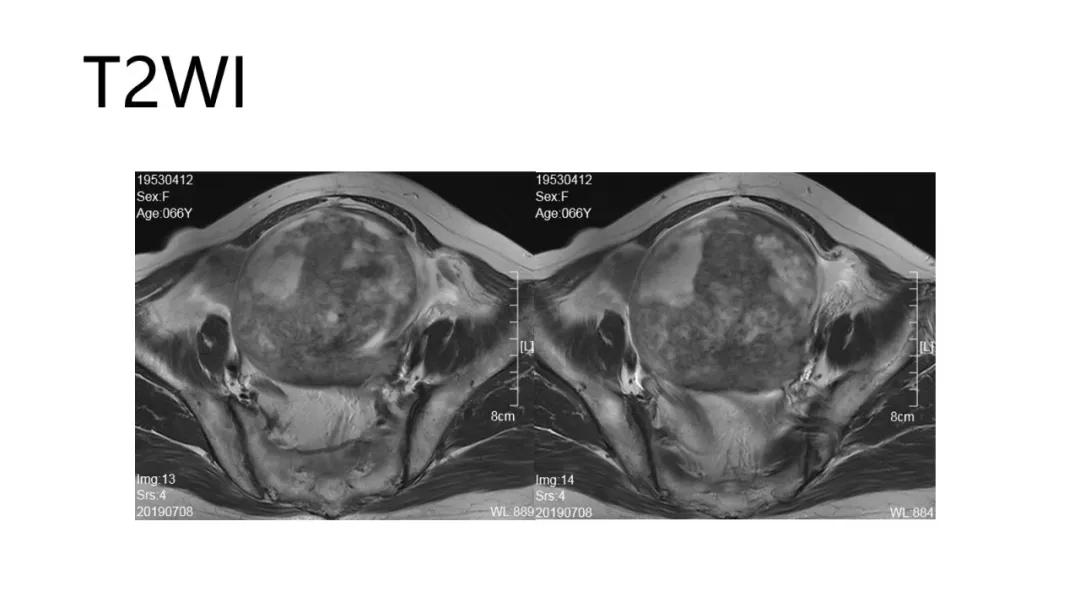

- 阴道不规则出血、闭经、量大:性索间质性肿瘤、子宫内膜样癌、透明细胞肿瘤

高雌激素症状:颗粒细胞瘤、卵泡膜细胞瘤(绝经期后出血及阴道不规则出血、性早熟、子宫内膜增生、乳房胀痛)